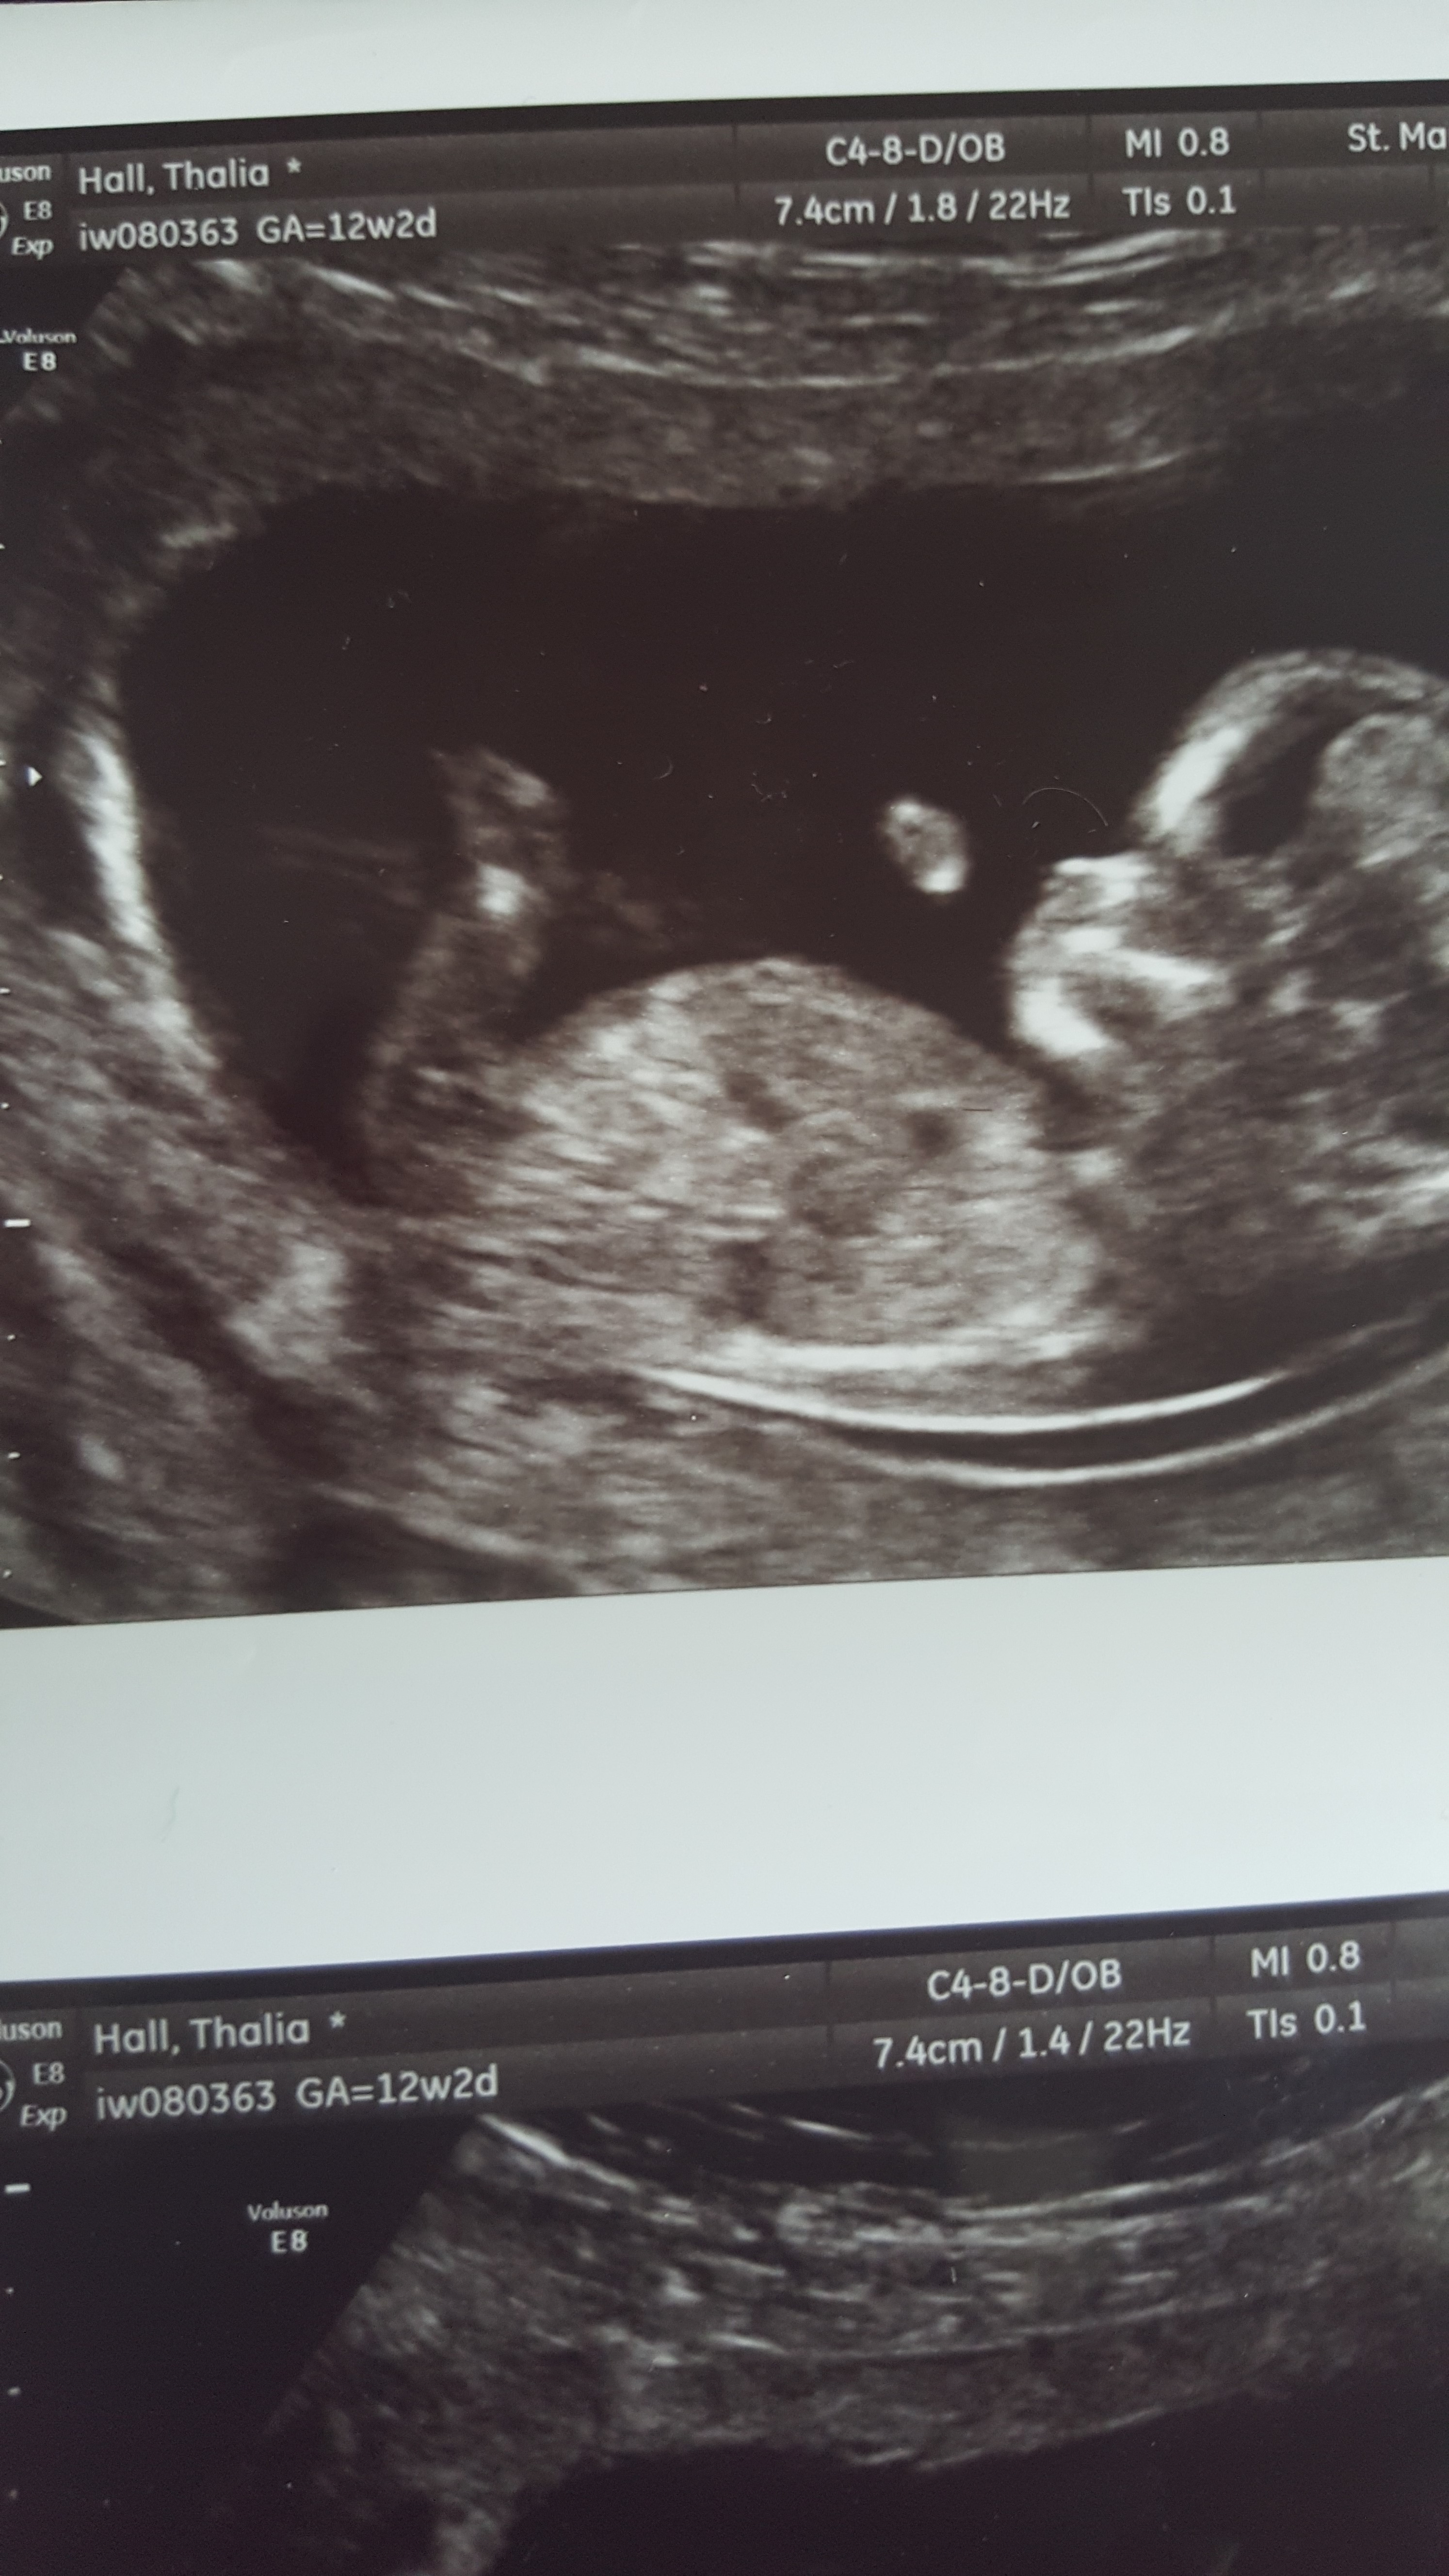

Hey everyone just had my 12 week scan and not sure if I can see the nub or not? Attachment 26804

Anyone have any ideas boy or girl?

No nub showing Im afraid :)

Ohhhh rubbish I thought it maybe the line going down to the leg meaning it would maybe a girl :fx:

There might be a vague girly nub there, but I'm not sure. FX!

not sure if that is the nub but would say gilr if it was x

Thinking maybe girl too if that's the nub I see

Girl guess